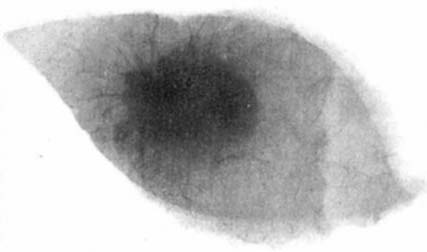

図1. 乳癌切除標本のX線写真.Salomonは,3,000例の切除標本のX線撮影を行ない,組織像と対比して,乳腺X線診断の基礎を築いた [1].

乳腺のX線撮影に世界で初めて取り組んだのは,ドイツの外科医 Albert Salomonで,1913年,手術症例約3,000例について,切除標本のX線撮影を行ない,肉眼所見,病理所見と綿密に対比した[1].その結果,X線写真で腫瘍の範囲が明らかになることを示し,また浸潤性硬性癌と限局性結節癌に分類した.これは画像所見と病理所見の対比という点で重要な業績であったが,当時のX線撮影の技術ではまだ十分なコントラストと画質が得られず,実際の臨床例の撮影報告されたのはさらに10年以上後のことであった.